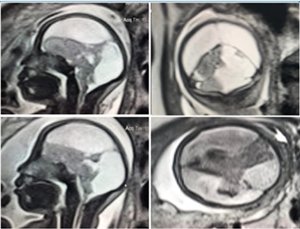

Não thoái hóa nước hay não úng thủy